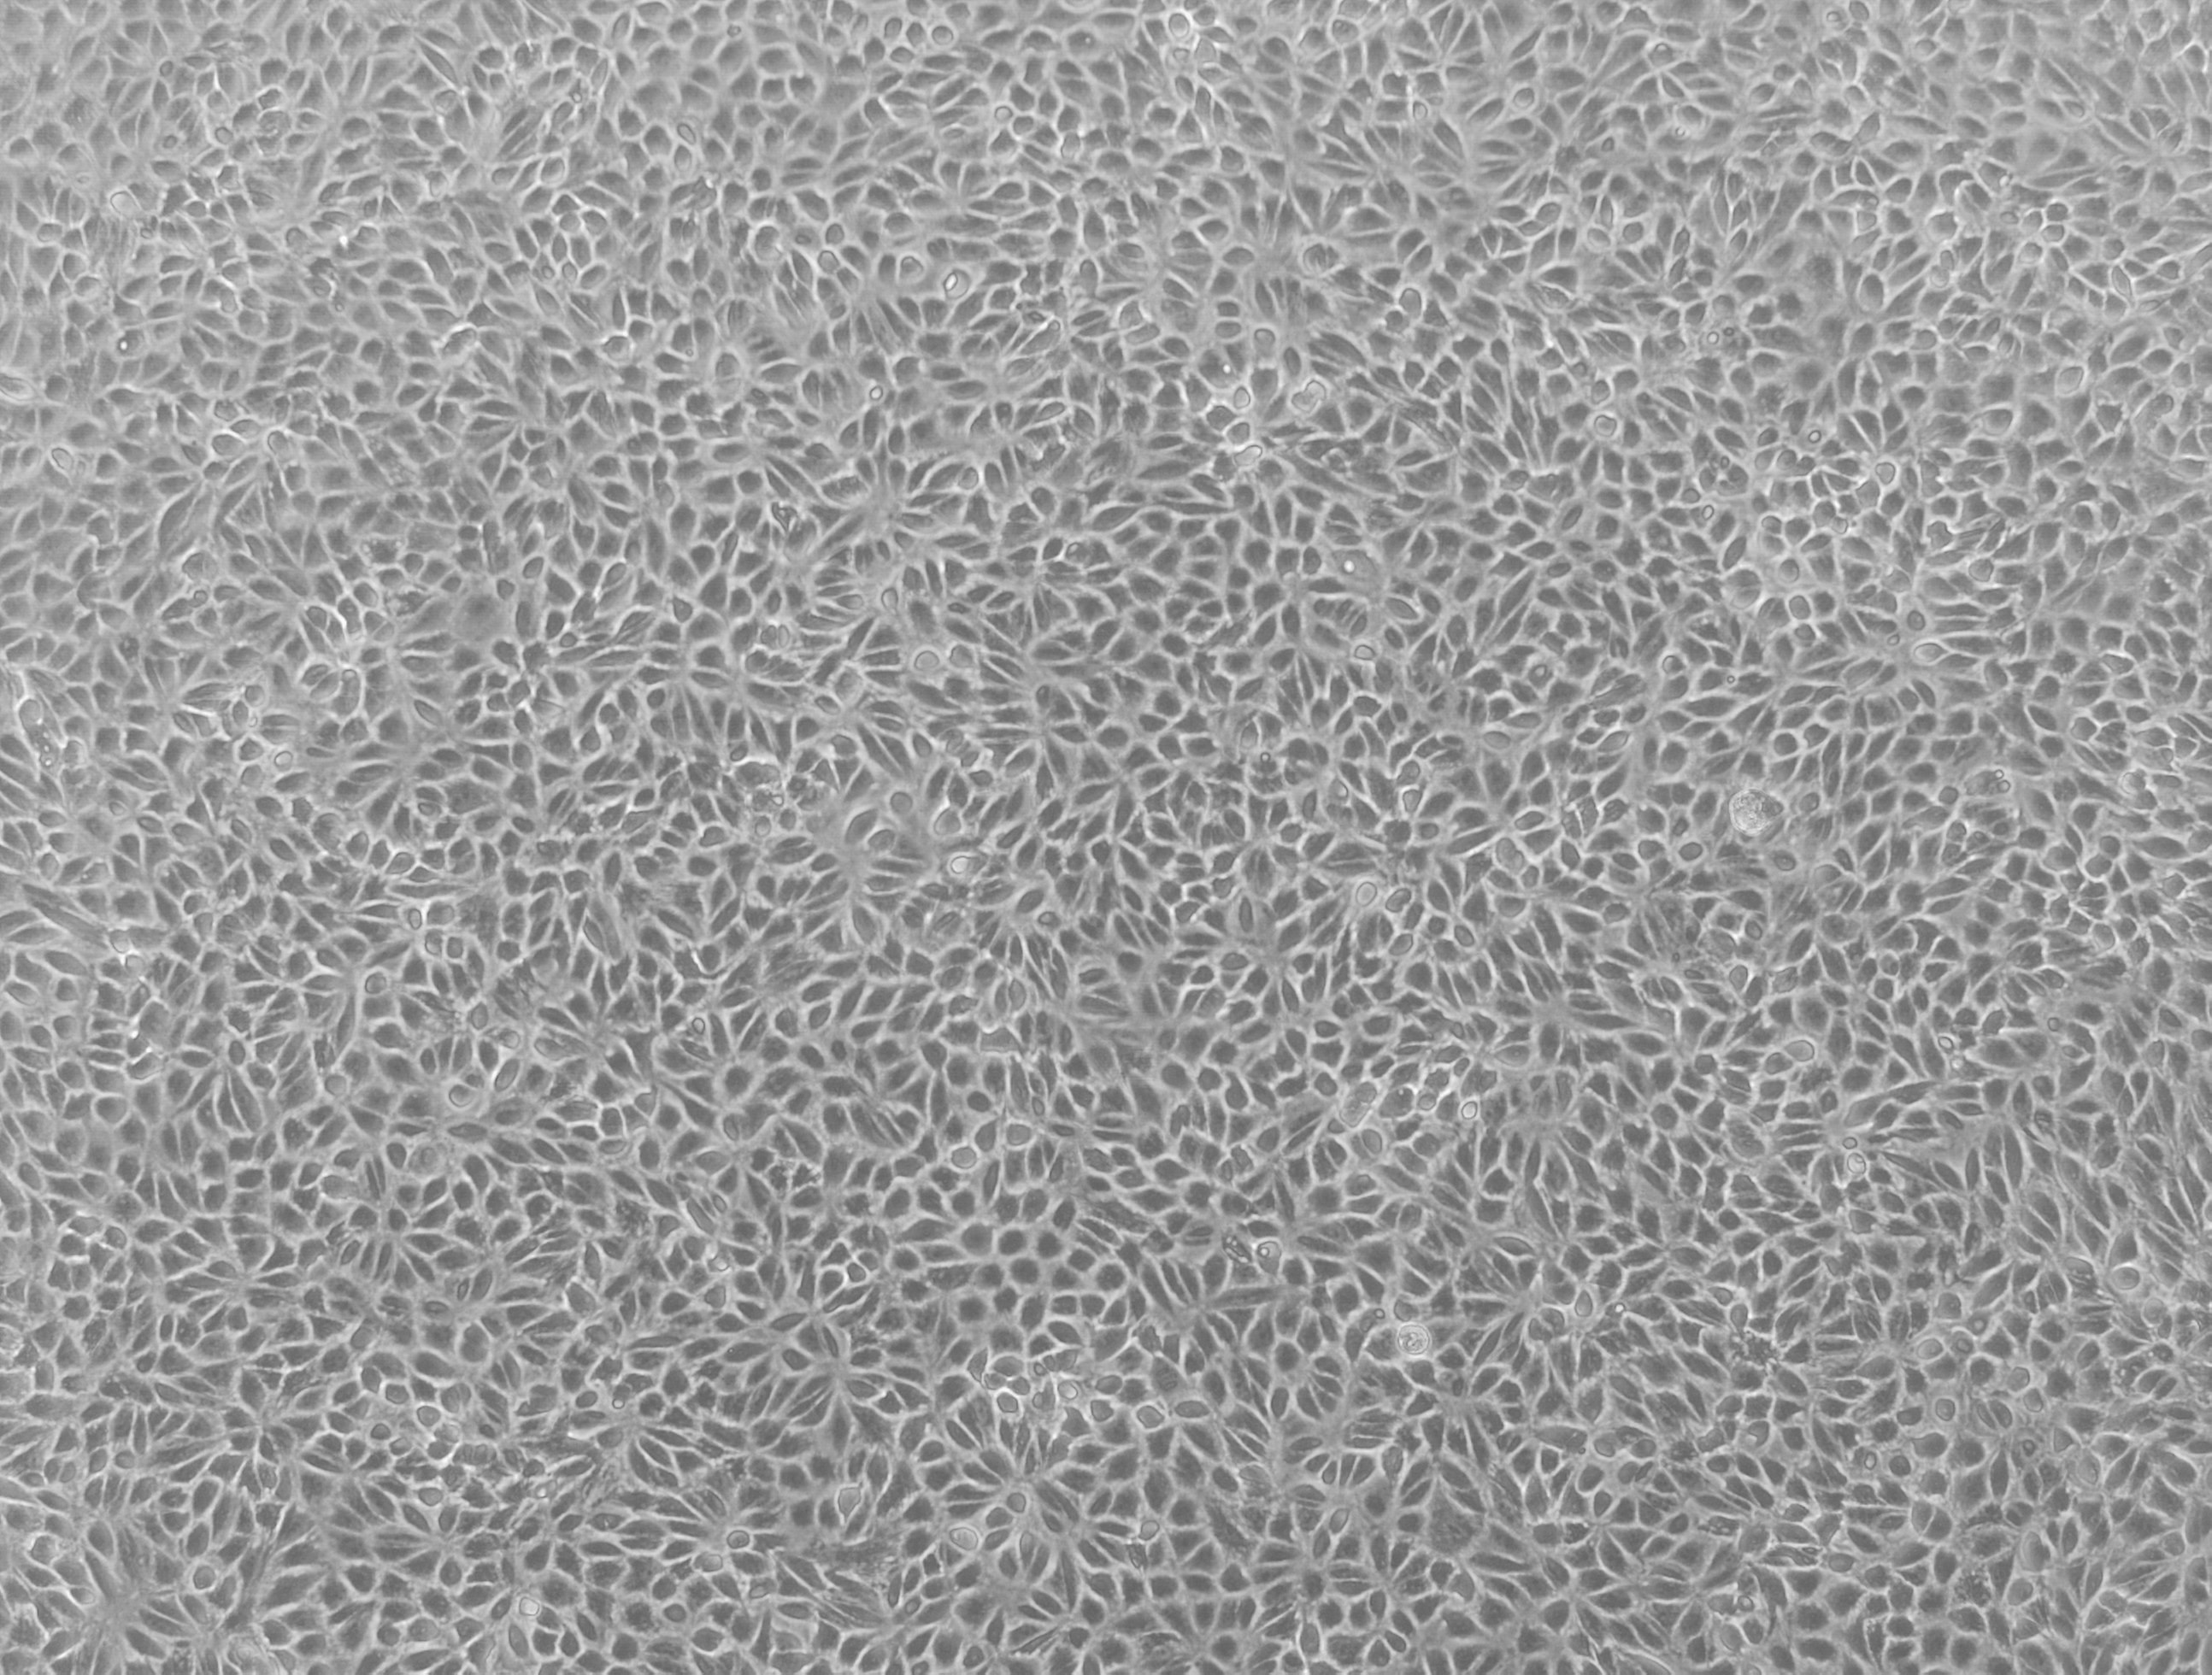

Figure 1.Human renal proximal tubule epithelial cells (RPTECs) are commonly used to predict human renal drug permeability and to investigate drug efflux. We have generated transporter knockout (KO) cell lines using CompoZr® Zinc Finger Nuclease (ZFN) technology in a proprietary renal proximal tubule epithelial cell line.